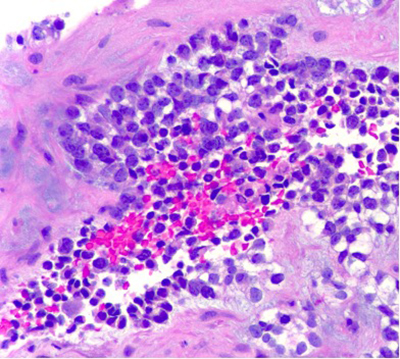

The aspirate was hypercellular and composed of small round cells, distributed in clusters of loosely cohesive clusters and as isolated cells. Moderate pleomorphism, hyperchromasia and variably prominent nucleoli were noted. On cell block preparation, the cytoplasm of these cells had a cleared appearance. Geographic necrosis was noted, with viable cells present in perivascular areas. Focally, there was an extracellular myxoid matrix.

Cell block preparation (400X)

The differential diagnosis is vast and includes many tumors that can present as small round cells, including conventional Ewing sarcoma. Recent studies have shown that CIC-DUX4 fusion sarcomas are clinically and morphologically different from Ewing sarcoma. CIC-DUX4 fusion sarcoma tends to arise deep in the soft tissue and in older patients (median: 40 years old), whereas Ewing sarcoma (median: 15 years old) arises in the bone in younger patients. Morphologically, the tumor cells exhibit mild pleomorphism, vesicular chromatin with variably prominent nucleoli, moderate amount of light eosinophilic cytoplasm and stroma with myxoid change. This is in contrast to Ewing sarcoma, which is usually monotonous with inconspicuous nucleoli. The immunohistochemical profile is also different. CD99 shows strong membranous staining in Ewing sarcoma, but is weak and variable in CIC-DUX4 fusion sarcoma. WT1 is usually negative in Ewing but is positive in most cases of CIC-DUX4 sarcoma. Recently, DUX4 immunohistochemistry has been shown to be positive, reflecting the fusion driving tumorigenesis. Molecular testing is ultimately required to identify one of the diagnostic translocations.